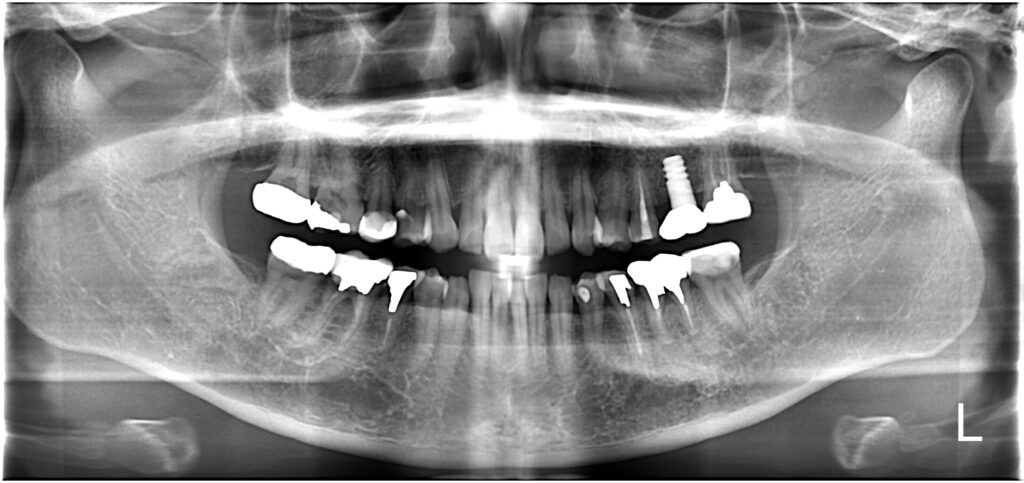

【A様】

パノラマ①

パノラマ②

パノラマ③

年齢 | 30代後半 |

性別 | 女性 |

主訴 | 歯を抜いた後、周りの歯を削ることなく噛めるようにしたい |

施術内容 | 右上第一大臼歯欠損部にインプラントを埋入し、ジルコニアクラウンを被せてあります |

治療期間 | 約1年(抜歯からジルコニアクラウン装着まで) |